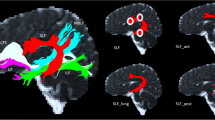

The dissections for all participants of the nvASD group are given in Fig. 1 and dissections of the vASD and TD participants can be found in the Online Resource 5. For visualization purposes, rendering of the streamlines was performed using the ‘tube’ render option of TrackVis with a radius of 0.15 mm. Examples of ROI placement are depicted in Fig. 2.

Dissections of nvASD participants. Manual deterministic tractography reconstructions from all participants of the nvASD group. Tracts reconstructed were the three segments of the arcuate fasciculus (AF) [Green = anterior, red = long, yellow = posterior segments], Frontal Aslant tract (FAT) [Cyan], Inferior Frontal Occipital Fasciculus (IFOF) [Purple], Inferior Longitudinal Fasciculus (ILF) [Dark blue] and Uncinate Fasciculus (UF) [Orange]. Abbreviations: L left. Montreal Neurological Institute space coordinates of the structural template slices are specified at the bottom of the image

Regions of Interest placement examples. Regions of interest (ROI) placements for manual deterministic tractography reconstructions of the selected tracts. Tracts reconstructed were the three segments of the arcuate fasciculus (AF), Frontal Aslant tract (FAT), Uncinate Fasciculus (UF), Inferior Longitudinal Fasciculus (ILF) and Inferior Frontal Occipital Fasciculus (IFOF)